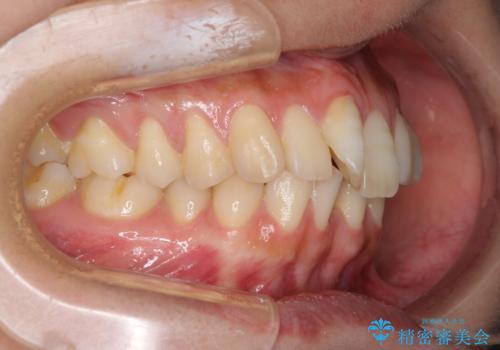

下顎前歯が2歯欠損しており、スペースになっており、上顎は叢生歯列となってしました。

奥歯の咬み合わせを考えると、理想的には2歯、最低でも1歯は下顎前歯の欠損部にインプラントやブリッジにより歯数を増やす必要がありました。

周囲の歯を削らないようにするためインプラントがおすすめとなりますが、歯根の移動が不十分な場合にはインプラントを埋入する幅が獲得できないため、その場合にはオールセラミックブリッジにより補綴治療を行うこととして、矯正治療を行うこととしました。